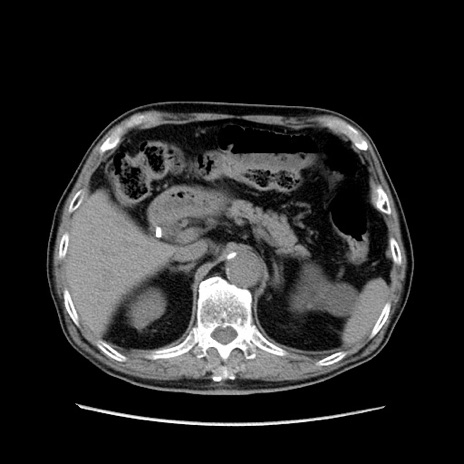

症例24(横断像)

【症例】80歳代男性

【主訴】左側腹部痛、嘔吐

【現病歴】本日早朝より左腹部に痛みあり。昼頃嘔吐認めたため、救急要請。

【既往歴】直腸癌(Mile手術)、胆摘

【身体所見】意識清明、BT 35.9℃、BP 221/93mmHg、SpO2 97%(RA) 、腹部:左ストーマ周囲に限局性の腹部膨隆あり。 膨隆部自発痛・圧痛あり・軟。

【データ】WBC 7700、CRP 0.09